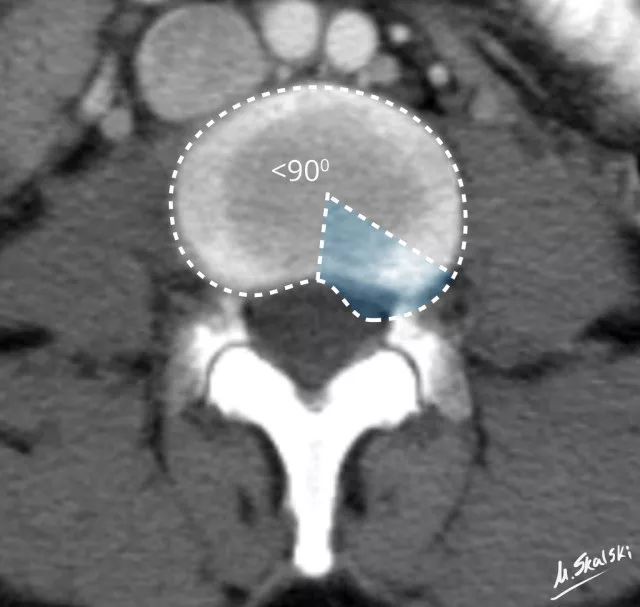

椎间盘突出的影像学定义为突出部分小于椎间盘边缘的25% , 并且基底部>突出部分的直径;突出椎间盘的两边与髓核的中心的夹角<90°